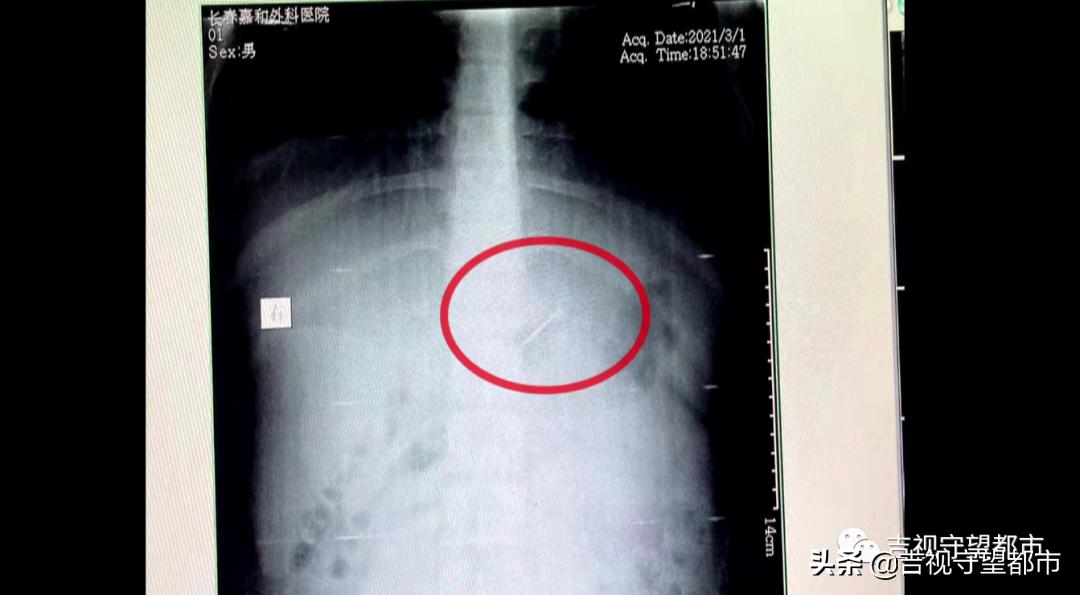

3月1号下午,我们接到了一个求助,说一个小孩吞了一枚钢钉,当地医院条件有限。孩子到了之后,我们先拍个片看了下这个钉子在什么部位,发现还是在胃里头。